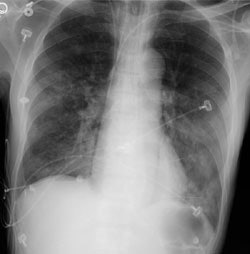

CT PE exam: Alternative diagnosis

The CT PE exam shown below demonstrates bilateral air space disease and a right pneumothorax that was not evident on the patients CXR (Click CXR to enlarge). The CT-PE exam can suggest an alternative diagnosis to explain the patients symptoms in 10-50% of cases.